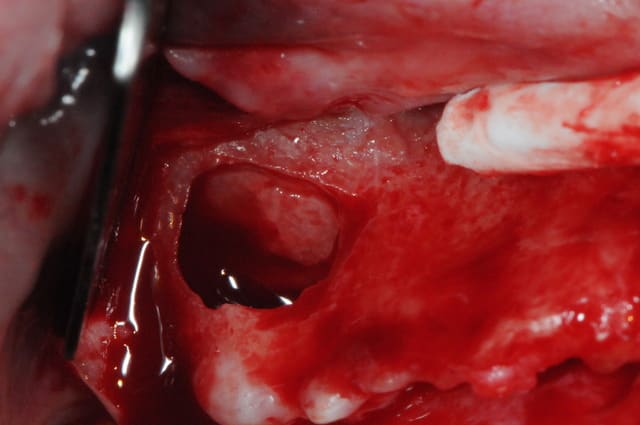

aspect des crêtes et début du sinus lift.

l'os était tellement fin qu'il n'y avait presque pas besoin de la piezo.

oui, comme tu peux le lire au début du poste sur le compte rendu opératoire, j'y ai placé du béta TCP (GRAFTEC et KASIOS) puis recouverts le tout avec une membrane COLLAGEN AT. j'en ai également mis en vestibulaire histoire de gagner encore en épaisseur.

non, j'ai à peine 1 mm d'épaisseur de crête, donc pas possible d'implanter. j'y retournerai dans 6 mois pour y mettre un implant et si possible y prélever un peu d'os pour pouvoir faire une analyse histologique.